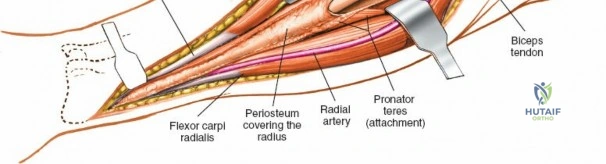

Managing the Radial Artery and Recurrent Leash

As the brachioradialis is retracted laterally, the radial artery and its venae comitantes are exposed lying deep in the middle part of the forearm, closely related to the medial edge of the wound. Begin dissection distally and work proximally. Just below the elbow joint, the radial artery gives off the recurrent radial artery and a leash of muscular branches that dive laterally into the brachioradialis.

This leash must be meticulously managed. Take time to isolate, ligate, and divide these vessels. Do not attempt to use electrocautery alone on the larger branches, and absolutely avoid blunt avulsion. Avulsion of these vessels from the main radial artery is a potent cause of difficult-to-control intraoperative bleeding and severe postoperative hematoma. Once the leash is divided, the brachioradialis can be fully mobilized laterally, exposing the deep muscular layer.

Exposing the proximal third of the radius requires extreme vigilance due to the proximity of the posterior interosseous nerve. The key anatomical landmark here is the insertion of the biceps tendon. Follow the biceps tendon distally to its insertion on the bicipital tuberosity of the radius. A small bursa lies just lateral to the tendon; incise this bursa to gain initial access to the proximal radial shaft. Because the radial artery lies superficial and medial to the tendon at this level, all deep dissection must remain strictly lateral to the biceps tendon.

For fracture fixation, a dynamic compression plate or locking compression plate is applied to the volar surface of the radius. The volar surface provides a flat, mechanically advantageous surface for plating and allows for excellent soft tissue coverage by the overlying muscle bellies upon closure. Ensure that the natural radial bow is meticulously restored during reduction to guarantee full postoperative pronation and supination.